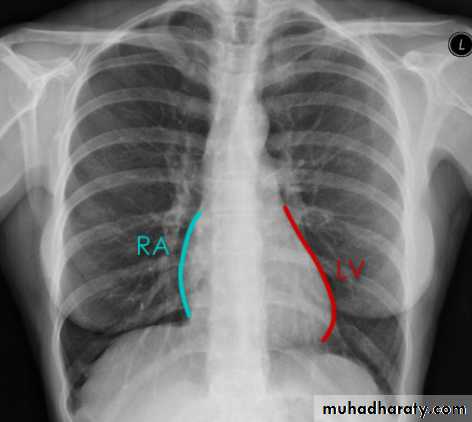

Cardiac borders in AP view

Mitral valve disease

Lymph adenopathy

14.cardiac border in AP view